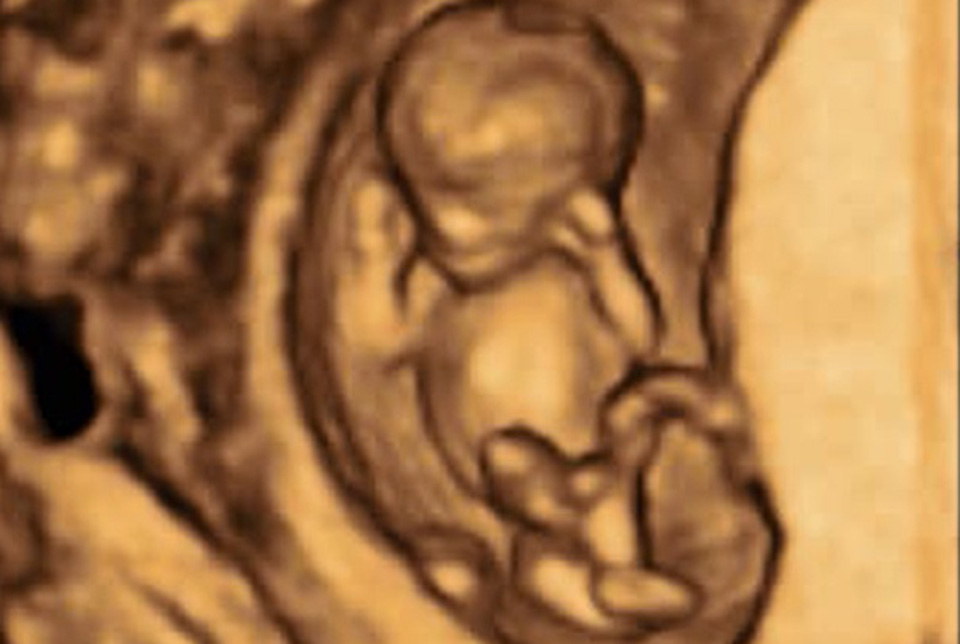

В последние 25 лет выяснилось, что частой причиной выкидышей и осложнений беременности у женщин является нарушение свёртываемости крови , кровотока и иммуноголическая несовместимость.

Клиника «нарушения свёртываемости крови в акушерстве и гинекологии» с частным гемореологической и гемостазиологической лабораторией является отправной точкой для семей с не сбывшимся желанием иметь детей, с повторяющимися выкидышами , неудачным ЭКО, со сложными пре- и эклампсиями, HELLP- синдромом, тромбозами, со склонностями к кровотечениям и другими врождёнными и приобретёнными нарушениями свёртываемости крови.